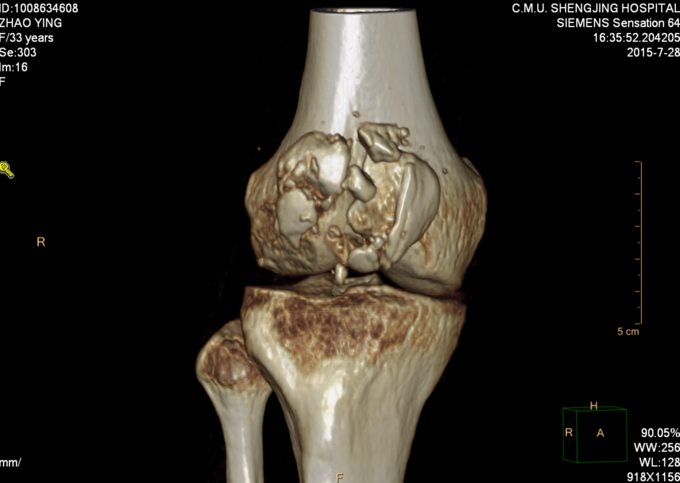

现病史:患者家属代诉于2015年7月23日5点发生车祸,车祸后致右膝部疼痛肿胀活动受限,当时无意识不清,120送至当地医院(辽中县医院),后为进一步治疗,急诊就诊于中国医科大学附属盛京医院,行X线片检查示:右髌骨开放性骨折,急诊给予清创缝合,观察患者病情稳定后,急诊以“右髌骨开放性骨折”为诊断收住我科·。伤来患者无头痛及发热,无咳嗽咳痰,无腹痛及恶心呕吐,饮食睡眠可,大小便正常。

右膝关节已清创缝合,缝合处约10cm不规则创口,右髌骨处软组织肿胀,右膝关节活动受限,右下肢皮肤感觉可,右下肢活动可,。右下肢足背动脉搏动良好,末梢血运良好,皮温正常。

右髌骨开放性骨折 患者急诊行清创缝合后,入院检查后,患者病情平稳,创口1至2天定期换药,观察患者创口愈合,患肢抬高,给予消炎消肿等对症治疗后。入院约一周后创口处无红肿,无渗出,全麻下行右髌骨开放性骨折切口复位张力带内固定术。